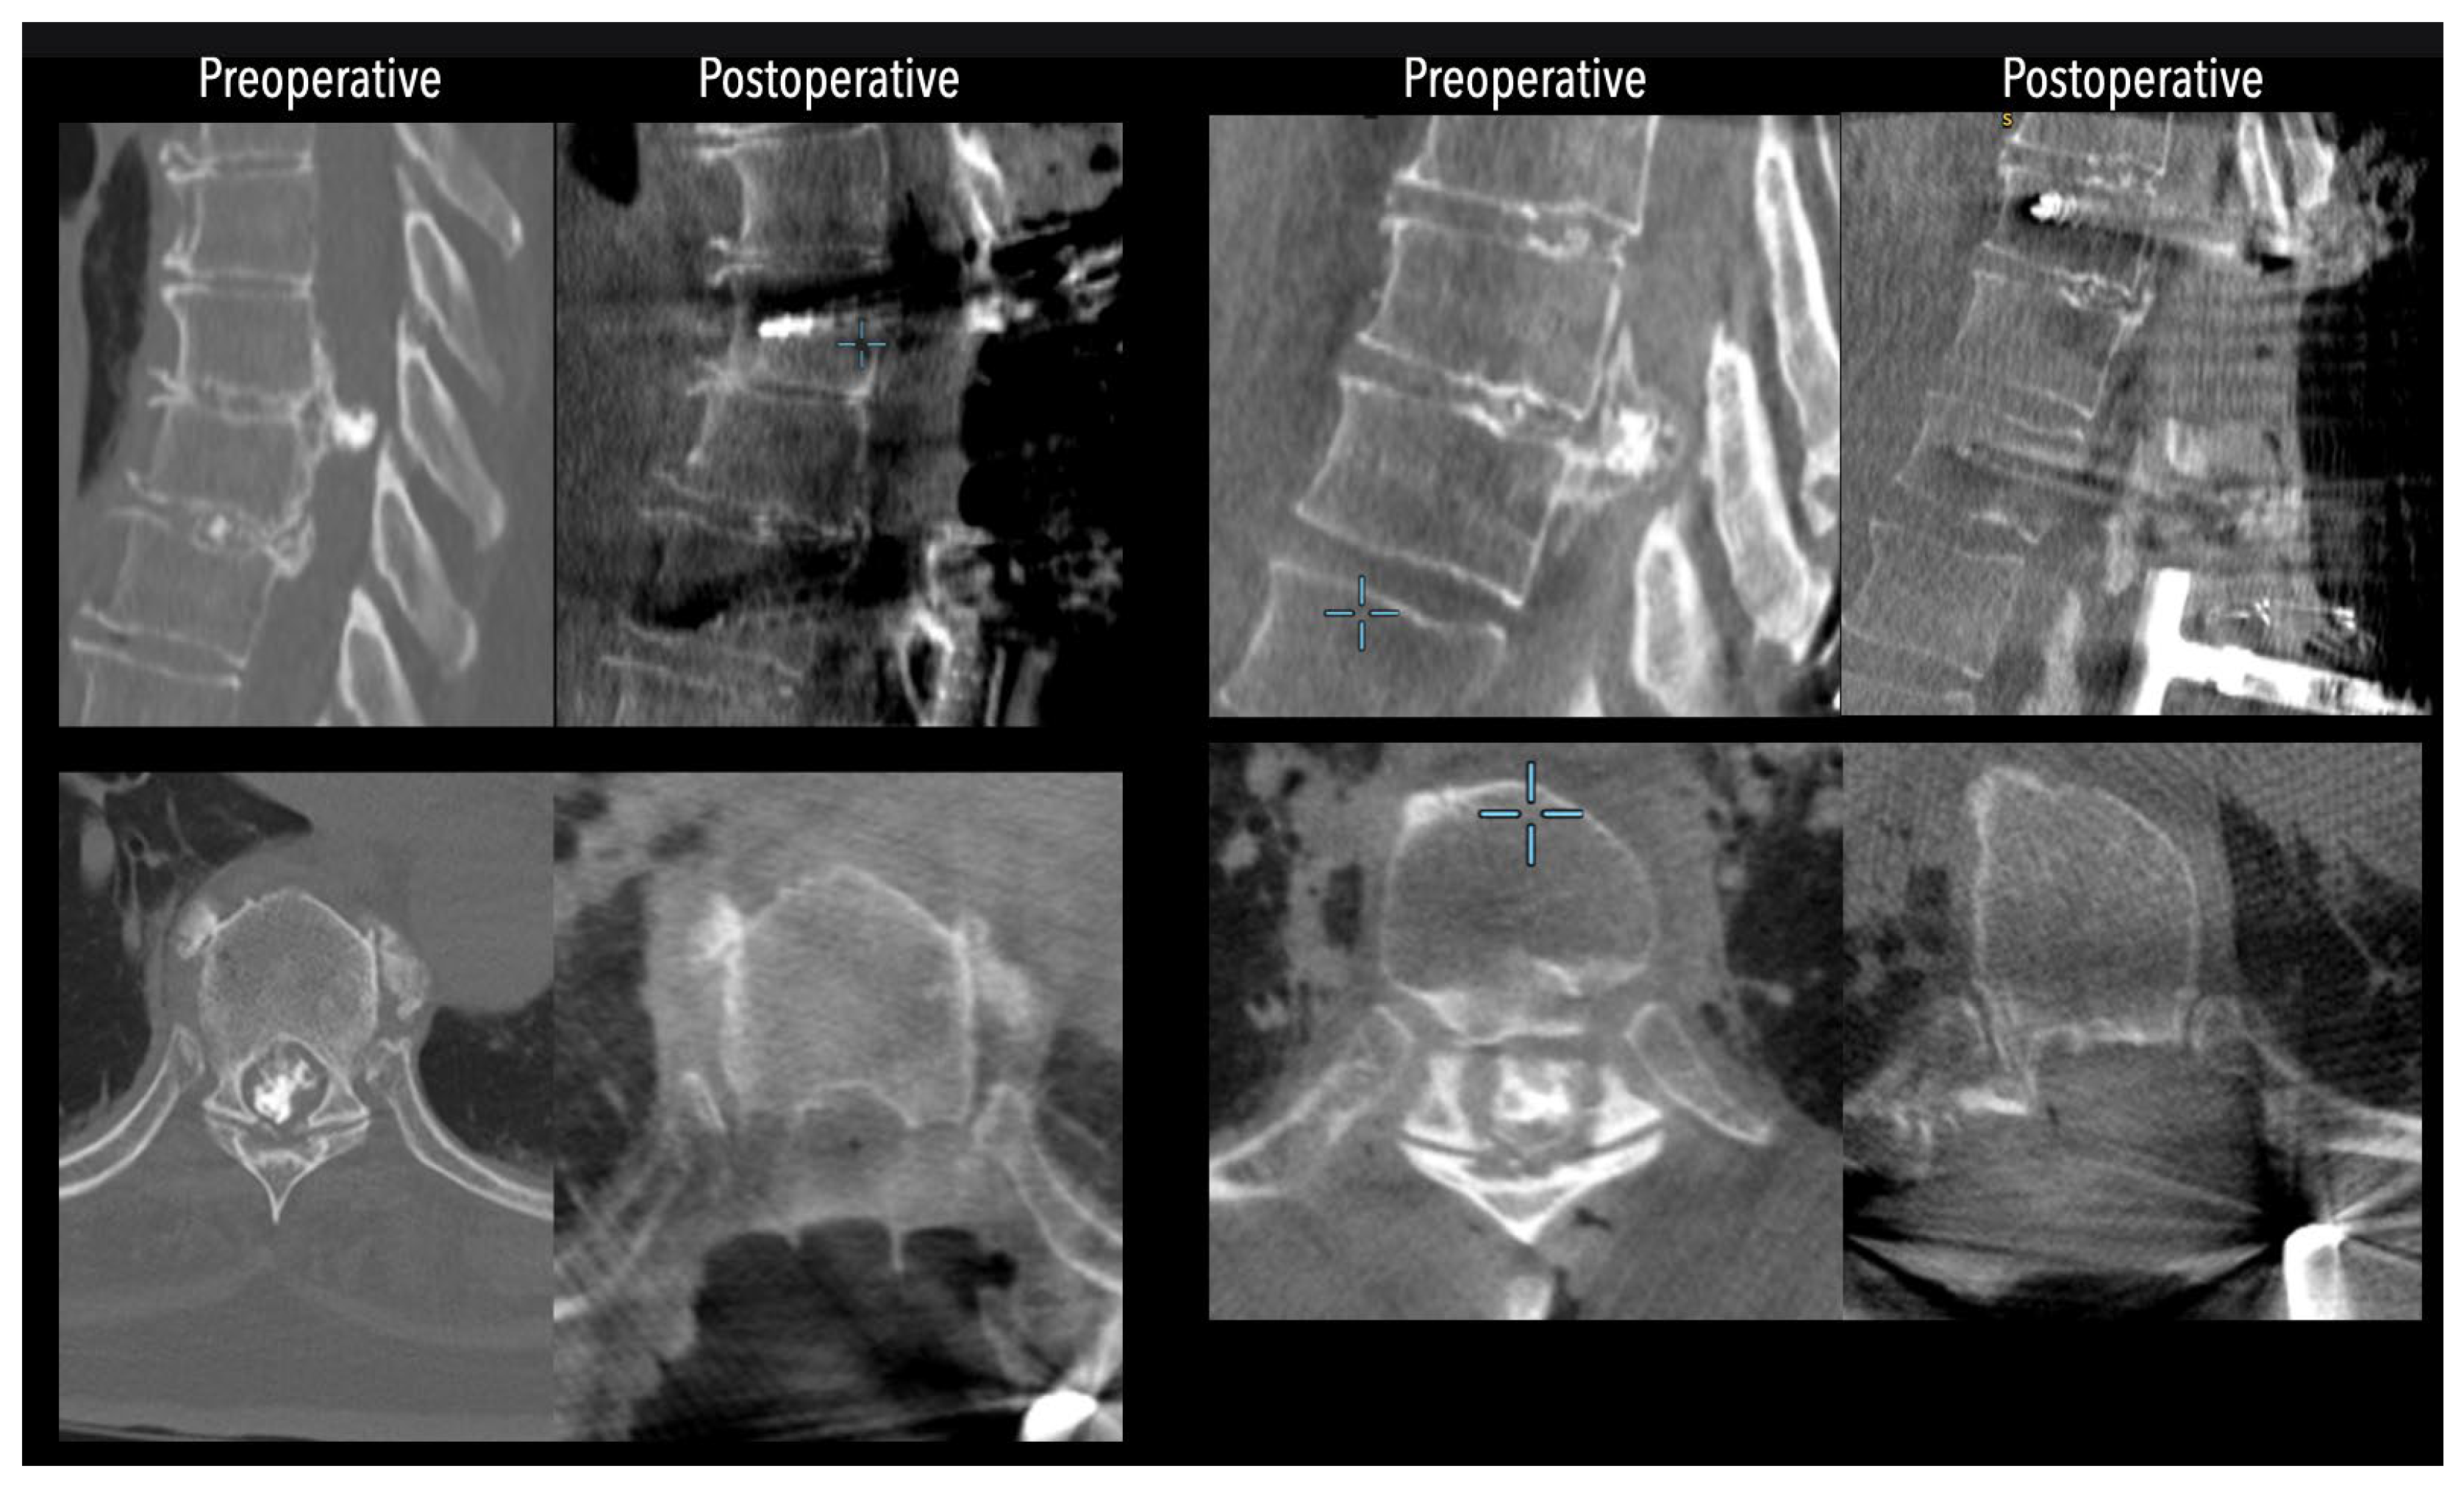

In three of the seven cases, the exiting nerve root at the level of the herniation was ligated due to poor visualization and transected extradurally to improve access. In the remaining four patients, the nerve root was either preserved or dissected intradurally using isocool bipolar diathermy and microsurgical scissors. With gentle medial retraction of the cord under gravity and protection using a micro-patty, the calcified disc was exposed. The ventral dura, when intact, was incised sharply and dissected from the disc surface where possible [Figures 2a,2b,3]. Disc removal was performed using a hockey-stick-shaped Misonix bone scalpel with constant irrigation, guided by intraoperative neuronavigation. The disc material was resected to a depth of 1–2 mm beyond the posterior vertebral wall to ensure adequate decompression. A second O-Arm spin was routinely performed following discectomy to confirm satisfactory decompression, especially given the limitations of the postoperative MRI due to the metal artefact [Figure 4, Figure 5 and Figure 6].

Figure 4. Comparative pre- and postoperative CT scans for two different patients (left and right), illustrating complete discectomy.